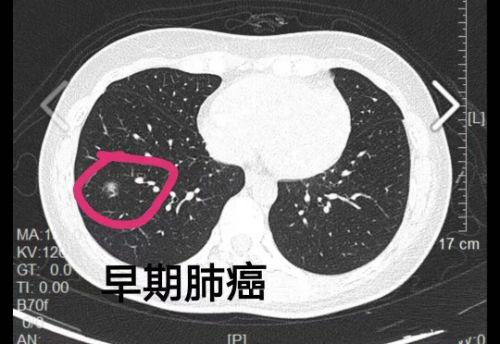

符合国家最新的新冠肺炎第七版诊疗方案提出的4条出院标准,即体温正常3天以上,呼吸道症状明显好转,肺部影像学明显改善以及连续两次核酸检测阴性,新冠肺炎治愈患者才可从定点治疗医院出院。